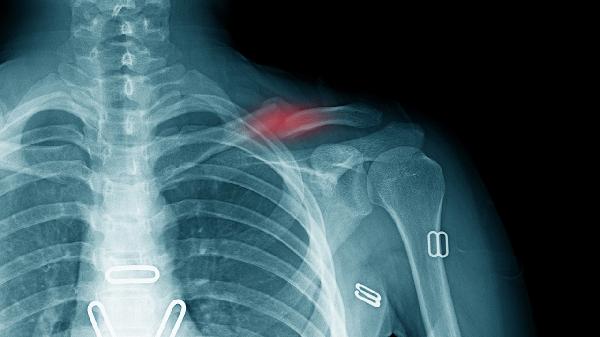

锁骨位置表浅,遭受直接暴力撞击如车祸、重物砸伤时易发生骨折。高处坠落或滑倒时手臂外展撑地,外力经肩关节传导至锁骨中段也可导致骨折。此类骨折多为横行或粉碎性,需通过X线检查确诊,急性期需用锁骨带固定4-6周,严重移位时需手术复位内固定。

对抗性运动如足球、橄榄球中肩部碰撞可能造成锁骨骨折,体操运动员跌倒时肩部着地也易发生。青少年骨骺未闭合时更易出现青枝骨折。运动相关骨折需立即停止活动,冰敷后使用八字绷带固定,康复期需逐步进行肩关节功能锻炼。